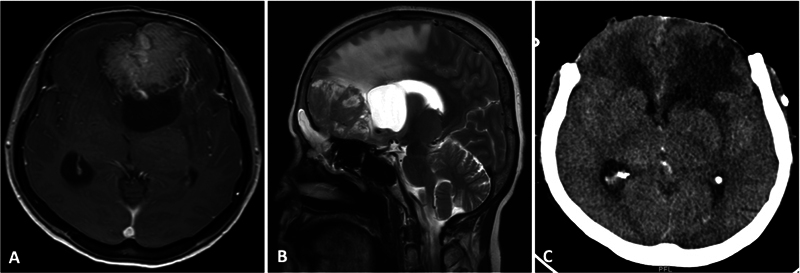

目的 颅内脑膜瘤占所有脑肿瘤的三分之一,是全世界神经外科手术最常见的适应症之一。大多数脑膜瘤症状不明显,病程较长。然而,有关脑膜瘤急诊手术结果的数据却很有限。本研究旨在介绍我们对急诊脑膜瘤患者进行紧急手术干预的经验。我们还分析了影响早期神经系统预后和并发症的因素。材料和方法 回顾性分析了 2015 年 1 月至 2019 年 12 月间所有非选择性急诊脑膜瘤手术。记录患者的人口统计学、临床和放射学细节,以便进行分析。手术过程、并发症和随访结果也包括在内,以便进行统计比较。结果 44 名患者符合研究条件,平均年龄(49.4±13.4)岁。患者的格拉斯哥昏迷量表(GCS)平均值为 13;47.7% 的病例出现感觉改变。最常见的病变位置是凸面(25 例,占 56.8%),平均肿瘤体积为 74.1 ± 36.5 mL。16例患者(36.4%)出现肿瘤周围水肿和肿块效应。随访 3 个月时的平均 Karnofsky 表情状态为 89.3 ± 18.2。患者年龄和肿瘤大小对预后没有影响。出现 GCS(P 0.03)和术后并发症(OR 25.71,CI 2.65-249.2,P 0.001)与不良预后有关。虽然没有统计学意义,但肿瘤分级较低也与较差的临床预后有关(P 0.20)。结论 脑膜瘤急诊手术的疗效和并发症发生率与常规择期手术相当。II/III 级脑膜瘤更有可能出现急性神经功能恶化,预后相对较差。在我们的研究中,GCS表现不佳和术后并发症是导致患者预后不佳的最关键因素。

Objective  Intracranial meningiomas constitute a third of all brain tumors and are among the most common indications for neurosurgical procedures performed worldwide. Most meningiomas present with an indolent, longstanding history. However, the data on outcomes of emergency surgeries for meningioma is limited. This study aims to present our experience of urgent surgical intervention in patients with meningiomas presenting acutely. We also analyze the factors influencing early neurological outcomes and complications. Materials and Methods  All nonelective meningioma surgeries done on an emergency basis between January 2015 and December 2019 were retrospectively reviewed. Patients' demography, clinical, and radiological details were recorded for analysis. The surgical procedure, complications, and follow-up outcomes were also included for statistical comparison. Results  Forty-four patients qualified for the study with a mean age of 49.4 ± 13.4 years. The average presenting Glasgow Coma Scale (GCS) was 13; 47.7% of cases presented with altered sensorium. The most common lesion location was convexity (25, 56.8%), and the mean tumor volume was 74.1 ± 36.5 mL. Gross peritumor edema with mass effect was seen in 16 patients (36.4%). The mean Karnofsky Performance Status at 3 months' follow-up was 89.3 ± 18.2. Patient age and tumor size did not affect outcomes. The presenting GCS of < 15 (odds ratio [OR] 8.8, confidence interval [CI] 0.95-80.72, p 0.03) and the occurrence of postoperative complications (OR 25.71, CI 2.65-249.2, p 0.001) were associated with unfavorable outcomes. Although not statistically significant, a poor tumor grade was also associated with worse clinical outcomes ( p 0.20). Conclusion  Emergency meningioma surgery has comparable outcomes and complication rates with routine elective procedures. Grade II/III meningiomas are more likely to present with acute neurological deterioration and carry a relatively worse prognosis. Poor presenting GCS and postoperative complications are the most critical factors associated with poor patient outcomes in our study.